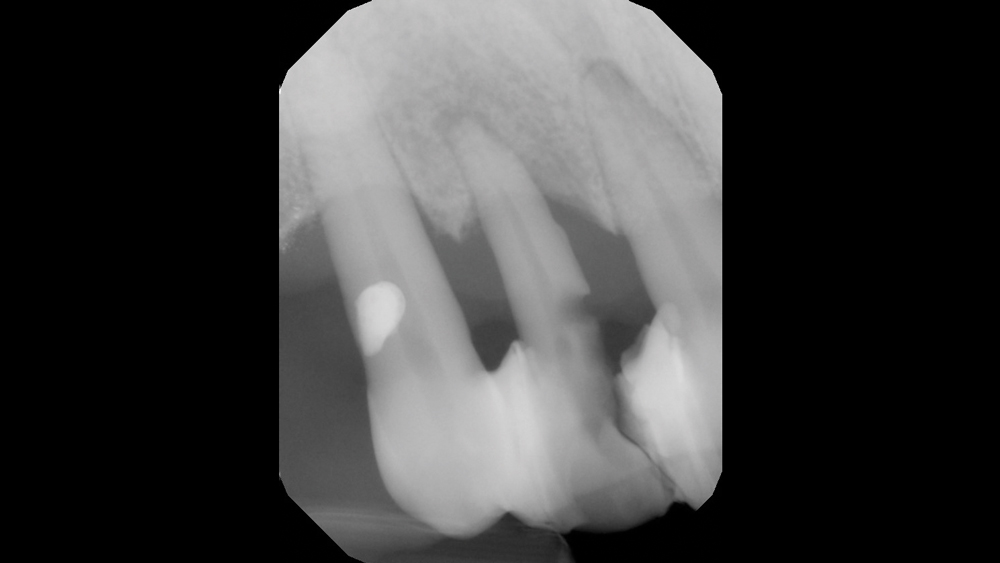

The chief complaint from my patient, Weldon, was missing teeth and gaps between his teeth. The preoperative evaluation showed periodontally involved and non-restorable maxillary right teeth #2–8 and significant periodontal bone loss, which would need to be addressed. The periodontal condition was stable in the patient’s left maxilla, and he was satisfied with the existing esthetics in that quadrant.

Bone Loss

There was significant bone loss on the right side of the maxilla, from the existing non-restorable central incisor back to the second molar. With this bone loss and mobility of the teeth, there was vertical and horizontal deficiency of the available bone. Options considered included an autogenous block graft to attempt to increase bone height and width. The second option was to work with the available bone, extract the non-restorable teeth on the right side of the maxillary arch, immediately place implants, and create esthetics with a longer prosthesis that includes pink-colored gingival areas. A BruxZir Solid Zirconia implant bridge was the optimal long-term solution because the entire prosthesis, including the gingival areas, is milled from a single block of high-strength solid zirconia, affording unmatched durability for this type of restoration. Although Weldon did not have a high smile line, he was attracted to a prosthetic design that included gingival areas to restore esthetics where tissue loss had occurred.